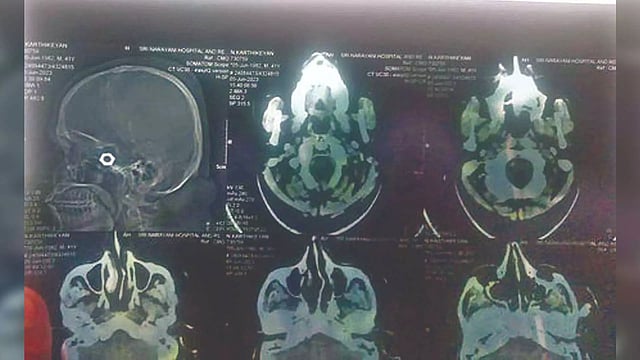

X-rays showing the nut lodged in the driver’s head

VELLORE: In a shocker, a truck driver, who was injured in an accident and underwent initial treatment at the Vellore Government Hospital and later shifted to a private clinic, was shocked to learn that there was a nut in his skull.

Karthikeyan’s relatives, who were not satisfied with the treatment at the GH, took him to a private clinic, and were shocked as the X-ray done at the private clinic showed the presence of a nut in the skull. The doctors allegedly sutured the wound without removing the foreign object.